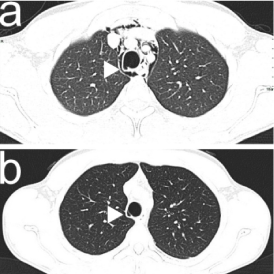

Chest X-ray (CXR) revealed clear lung fields, pneumomediastinum (PM) and emphysema in the soft tissues between the muscles of the neck (Figure 1a). Pulmonary computed tomography (CT) without contrast showed pneumomediastinum (PM), i.e. air dissecting tissue planes extending in the soft tissues of the neck, including the muscles, the nerves, the right rear second back rib and the ipsilateral front first and second anterior rib, all the mediastinal recesses (also anterior) and the bilateral peribronchial and paraesophageal spaces until the diaphragmatic hiatus. CT also showed a solution of continuity of the right postero-lateral portion of the trachea with adjacent minimum hypo-dense material (Figures 2a, 3a, 4a). In emergency department, the application of human fibrin glue by means of bronchoscopy was used to seal the tracheal lesion. CXR showed complete resolution of the PM and subcutaneous emphysema after 12 days (Figure 1b). Chest CT without contrast also revealed complete resolution at 15 days (Figures 2b, 3b, 4b).

Figure 3. PM and the solution of continuity (white arrow-head) of the right postero-lateral portion of the trachea (a); complete resolution of PM, closure of the tracheal solution of continuity with residual small pocket area (10 x 5 x 5 mm) (white arrow-head) on the right lateral side of the tracheal wall adjacent to the previous tracheal laceration treated endoscopically, and a good barrage of scar tissue at that level on CT scan in axial plane (b).